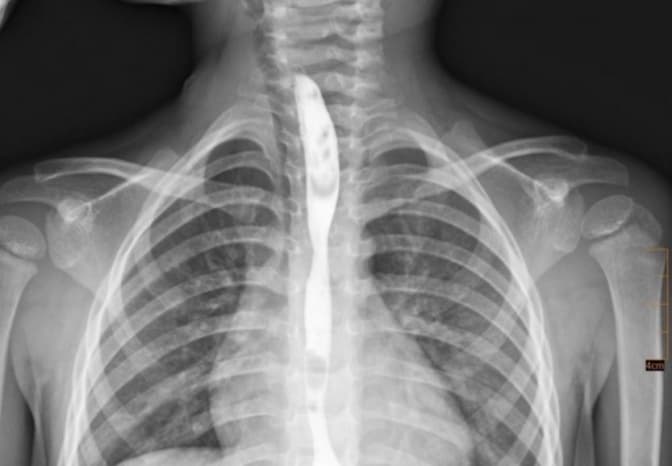

Як зазначають у лікарні, через тяжкість ураження та неможливість харчування через рот команда торакальних хірургів виконала накладання гастростоми. Це забезпечило повноцінне харчування без додаткового навантаження на стравохід та стабілізувало стан пацієнта. Згодом у дитини розвинувся критичний стеноз стравоходу — сильне звуження, яке повністю унеможливлювало прийом їжі.

Після обговорення мультидисциплінарною командою було проведено серію балонних дилатацій — малоінвазивних ендоскопічних втручань, під час яких уражену ділянку поступово розширюють спеціальним балоном без розрізів.